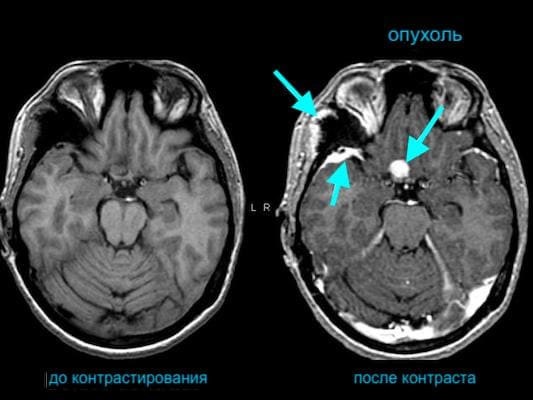

В большинстве случаев диагностики с помощью радиоволн и магнитных полей достаточно для обнаружения отклонений от нормы во внутренних органах, суставах, мозговых структурах и позвоночнике. Но иногда возникает необходимость в получении максимально точного и детализированного изображения, и тогда врач рекомендует метод с контрастированием. Введенное вещество оказывает влияние на свойства молекул воды в исследуемой области, улучшая тем самым визуализацию и позволяя найти мельчайшие аномалии за счет усиленного сигнала.

Показывает ли МРТ без контраста опухоли?

Выявить новообразования можно и без введения в организм пациента специальных препаратов. Однако в некоторых случаях, например, при небольших размерах опухоли либо её сложном расположении, требуется усиление, чтобы максимально точно установить вид и стадию патологии. Также исследование назначают для определения злокачественности и при принятии решения об оперативном вмешательстве.